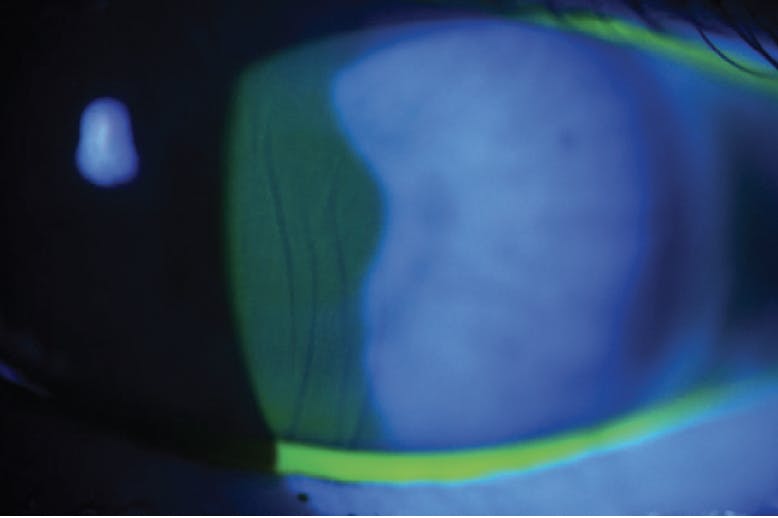

The latest version of the Visian ICL, the Evo Visian ICL, has a central port located on the lens (Figure 4) that would eliminate the need for a PI.12 The central port helps maintain the health of the crystalline lens by preserving the natural flow of aqueous humor across the anterior lens capsule.12